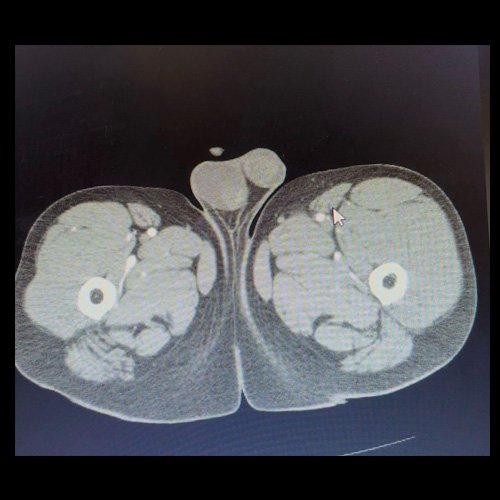

• AngioTAC de miembros inferiores (Día 0): Ateromatosis parietal calcificada parcheada en todo el territorio aorto-ilíaco-femoral bilateral. LADO DERECHO: Arteria ilíaca interna: de calibre y trayecto conservado, permeable. Arterias ilíaca externa y femoral común: de calibre y trayecto conservados, permeables. Arterias circunfleja ilíaca superficial y epigástrica superficial: de calibre y trayecto conservados, permeables. Arteria femoral superficial: de calibre y trayecto conservado, permeable. Arteria femoral profunda: de calibre y trayecto conservado, permeable. Arterias circunflejas femoral medial y lateral: de calibre y trayecto conservados, permeables. Arteria poplítea: de calibre y trayecto conservado, permeable. Arteria tibial anterior: de calibre y trayecto conservado, permeable. Arteria tibial posterior: de calibre y trayecto conservado, permeable. Cambios artrodegenerativos coxo-femorales y tricompartimentales en la rodilla. Signos de entesopatía cuadricipital distal. No se observan alteraciones a nivel de los grupos musculares visualizados. La disposición del tejido graso es normal. LADO IZQUIERDO: En fase angiográfica se observa menor calibre y opacificación de las arterias femoral superficial y profunda, poplítea y de sus ramas musculares en muslo y pierna en comparación con el miembro contralateral, con opacificación arterial preservada. En fase venosa se evidencia mayor la densidad endovascular de las mismas hasta el tercio distal de la pierna, donde se logran identificar a las arterias peronea, tibial anterior y tibial posterior. Se evidencia un defecto de relleno de la vena ilíaca común izquierda, en su nacimiento, en relación a trombosis venosa profunda. No se identifica compromiso de la porción visualizada de la vena cava inferior ni del sistema venoso ilíaco contralateral. Se visualiza aumento del tamaño de todos los grupos musculares del muslo izquierdo con respecto al contralateral y retardo de la concentración de contraste, asociado a edema de los tejidos blandos superficiales. Reticulación de la grasa de la región inguinal. Cambios artrodegenerativos coxo-femorales y tricompartimentales en la rodilla. Signos de entesopatía cuadricipital distal. No se observan alteraciones a nivel del fémur ni de las porciones visualizadas de la tibia y el peroné.

• AngioTAC de miembros inferiores (Día 2): Ateromatosis parietal calcificada parcheada en todo el territorio aorto-ilíaco-femoral bilateral. LADO DERECHO: Arteria ilíaca interna: de calibre y trayecto conservado, permeable. Arterias ilíaca externa y femoral común: de calibre y trayecto conservados, permeables. Arterias circunfleja ilíaca superficial y epigástrica superficial: de calibre y trayecto conservados, permeables. Arteria femoral superficial: de calibre y trayecto conservado, permeable. Arteria femoral profunda: de calibre y trayecto conservado, permeable. Arterias circunflejas femoral medial y lateral: de calibre y trayecto conservados, permeables. Arteria poplítea: de calibre y trayecto conservado, permeable. Arteria tibial anterior: de calibre y trayecto conservado, permeable. Arteria tibial posterior: de calibre y trayecto conservado, permeable. Vena ilíaca primitiva: 13 mm, vena ilíaca externa 11 mm, vena ilíaca interna 7 mm. LADO IZQUIERDO: En esta ocasión, en fase angiográfica se observa de calibre y opacificación conservada de las arterias femoral superficial y profunda, poplítea y de sus ramas musculares en muslo y pierna. En fase venosa se evidencia un defecto de relleno endoluminal de la vena primitiva izquierda que impresiona extenderse actualmente a la vena iliaca externa, a la vena femoral superficial y poplítea, hasta nivel del hueco homonimo, las cuales se visualizan aumentadas de calibre con respecto a sus contralaterales, en relación a trombosis venosa profunda. Se sugiere cotejar con ecodoppler de miembros inferiores. No se identifica compromiso de la porción visualizada de la vena cava inferior ni del sistema venoso ilíaco contralateral. Se visualiza dispositivo vascular en VCI (filtro VCI), infrayacente a las venas renales. Presenta aumento del diámetro del muslo izquierdo con respecto a su contralateral, asociado a edema de los tejidos blandos superficiales. Reticulación de la grasa de la región inguinal a predominio izquierdo con algunas burbujas aéreas. Se observa inmediatamente infrayacente a los antes mencionado, un área hiperdensa que realza en fase venosa, con centro hipodenso, que mide 2.2 cm x 1.4 cm, ya visualizado en tomografía previa. Cambios artrodegenerativos coxo-femorales y tricompartimentales en la rodilla. Signos de entesopatía cuadricipital distal. No se observan alteraciones a nivel del fémur ni de las porciones visualizadas de la tibia y el peroné. Arteria ilíaca interna: de calibre y trayecto conservado, permeable. Arterias ilíaca externa y femoral común: de calibre y trayecto conservados, permeables. Arterias circunfleja ilíaca superficial y epigástrica superficial: de calibre y trayecto conservados, permeables. Arteria femoral superficial: de calibre y trayecto conservado, permeable. Arteria femoral profunda: de calibre y trayecto conservado, permeable. Arterias circunflejas femoral medial y lateral: de calibre y trayecto conservados, permeables. Arteria poplítea, tibial anterior y tibial posterior: de calibre disminuido con respecto a su contralateral, permeables. Vena ilíaca primitiva: 14 mm, vena ilíaca externa 17 mm, vena ilíaca interna 9 mm. Calcificaciones en conducto inguinal bilateral. Hidrocele bilateral.

Angio TAC de miembros inferiores (Día 0)